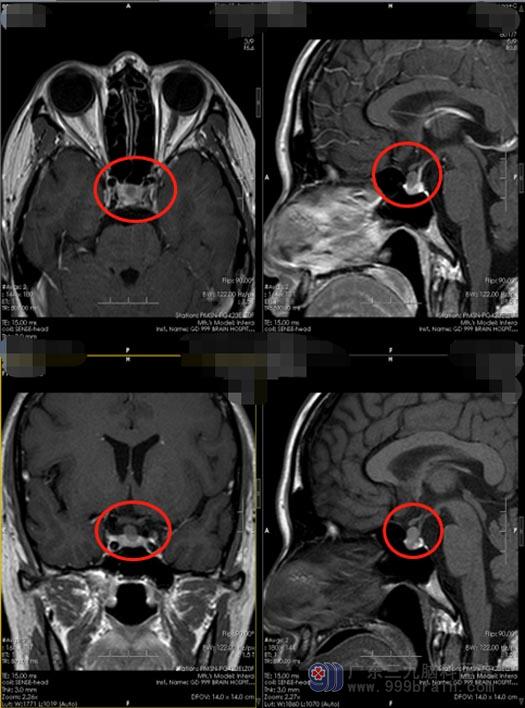

知道了原因,小刘非常紧张,“喝水多居然是脑子里出现了问题”,她忐忑不安地在网上搜集相关的疾病知识,越看越害怕。在朋友的安慰和介绍下,小刘来到了广东三九脑科医院神经外五科,进一步垂体影像检查发现:垂体前叶上缘占位性病变,考虑 Rathke’s囊肿可能性大,待排微腺瘤囊变;CT血管成像检查意见:鞍区结节状占位性病变。